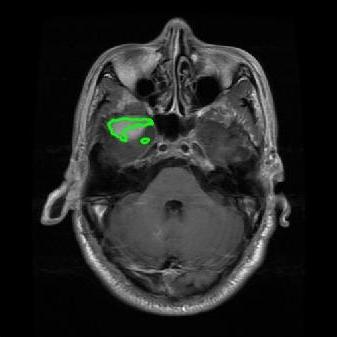

From the above discussions, we have discovered the significant potential of applying Retinex theory to image segmentation and explored its fundamental differences from traditional models. Traditional image segmentation models typically focus on the impact of intensity information on the segmentation results. Therefore, when faced with complex segmentation scenarios, the segmentation results are often affected by lighting, artifacts, and unclear boundaries in the image. As shown in Fig. 1, we present the results of the classical local model LIF [ZHANG20101199] for segmenting brain tumor images along with surrounding tissue edema. The irregular ring-like enhancement caused by the edematous tissue leads to irregular boundaries and low contrast in the images. Consequently, the LIF model can only identify the central necrotic and liquefied regions of the tumor, failing to detect the boundaries and becoming trapped in local minima. In this paper, we draw inspiration from the Retinex theory, which is widely applied in the field of image enhancement. According to Retinex theory, the reflectance component characterizes the intrinsic structural properties of the observed image and preserves texture information independent of illumination variations. By integrating this reflectance component into the level set framework, our model achieves robust segmentation of medical images even under severe intensity inhomogeneity. In addition, a linearized Structural-Prior is proposed to restore intensity consistency and capture local geometric features, thereby improving boundary localization in complex or blurred regions. Furthermore, a relaxed binary level set representation is employed to enhance robustness against noise and to enable accurate tracking of complex contours. Based on these innovations, we propose a novel variational reflectance-based level set model (RefLSM) that simultaneously corrects bias fields and performs segmentation. Experimental results demonstrate that RefLSM significantly outperforms conventional level set methods in both segmentation accuracy and robustness. We present the results of our model segmenting the two brain tumor images mentioned above in Fig. 2.

To address the challenge of segmenting images with severe intensity inhomogeneity, we propose a linearized structural prior that directly operates on the reflectance component . Reflectance-based structural information is more robust to illumination variations and bias field distortions, helping preserve weak edges and subtle anatomical boundaries. As shown in Fig. 2, our method can accurately delineate tumor boundaries and surrounding edema even under severe inhomogeneity, where traditional intensity-based models often fail. The proposed prior aligns smoothed reflectance gradients with data-driven directions, enhancing inter-region contrast, preserving weak edges, and stabilizing the evolution of . Formally, we define the linear structure operator as the gradient field of the smoothed reflectance: